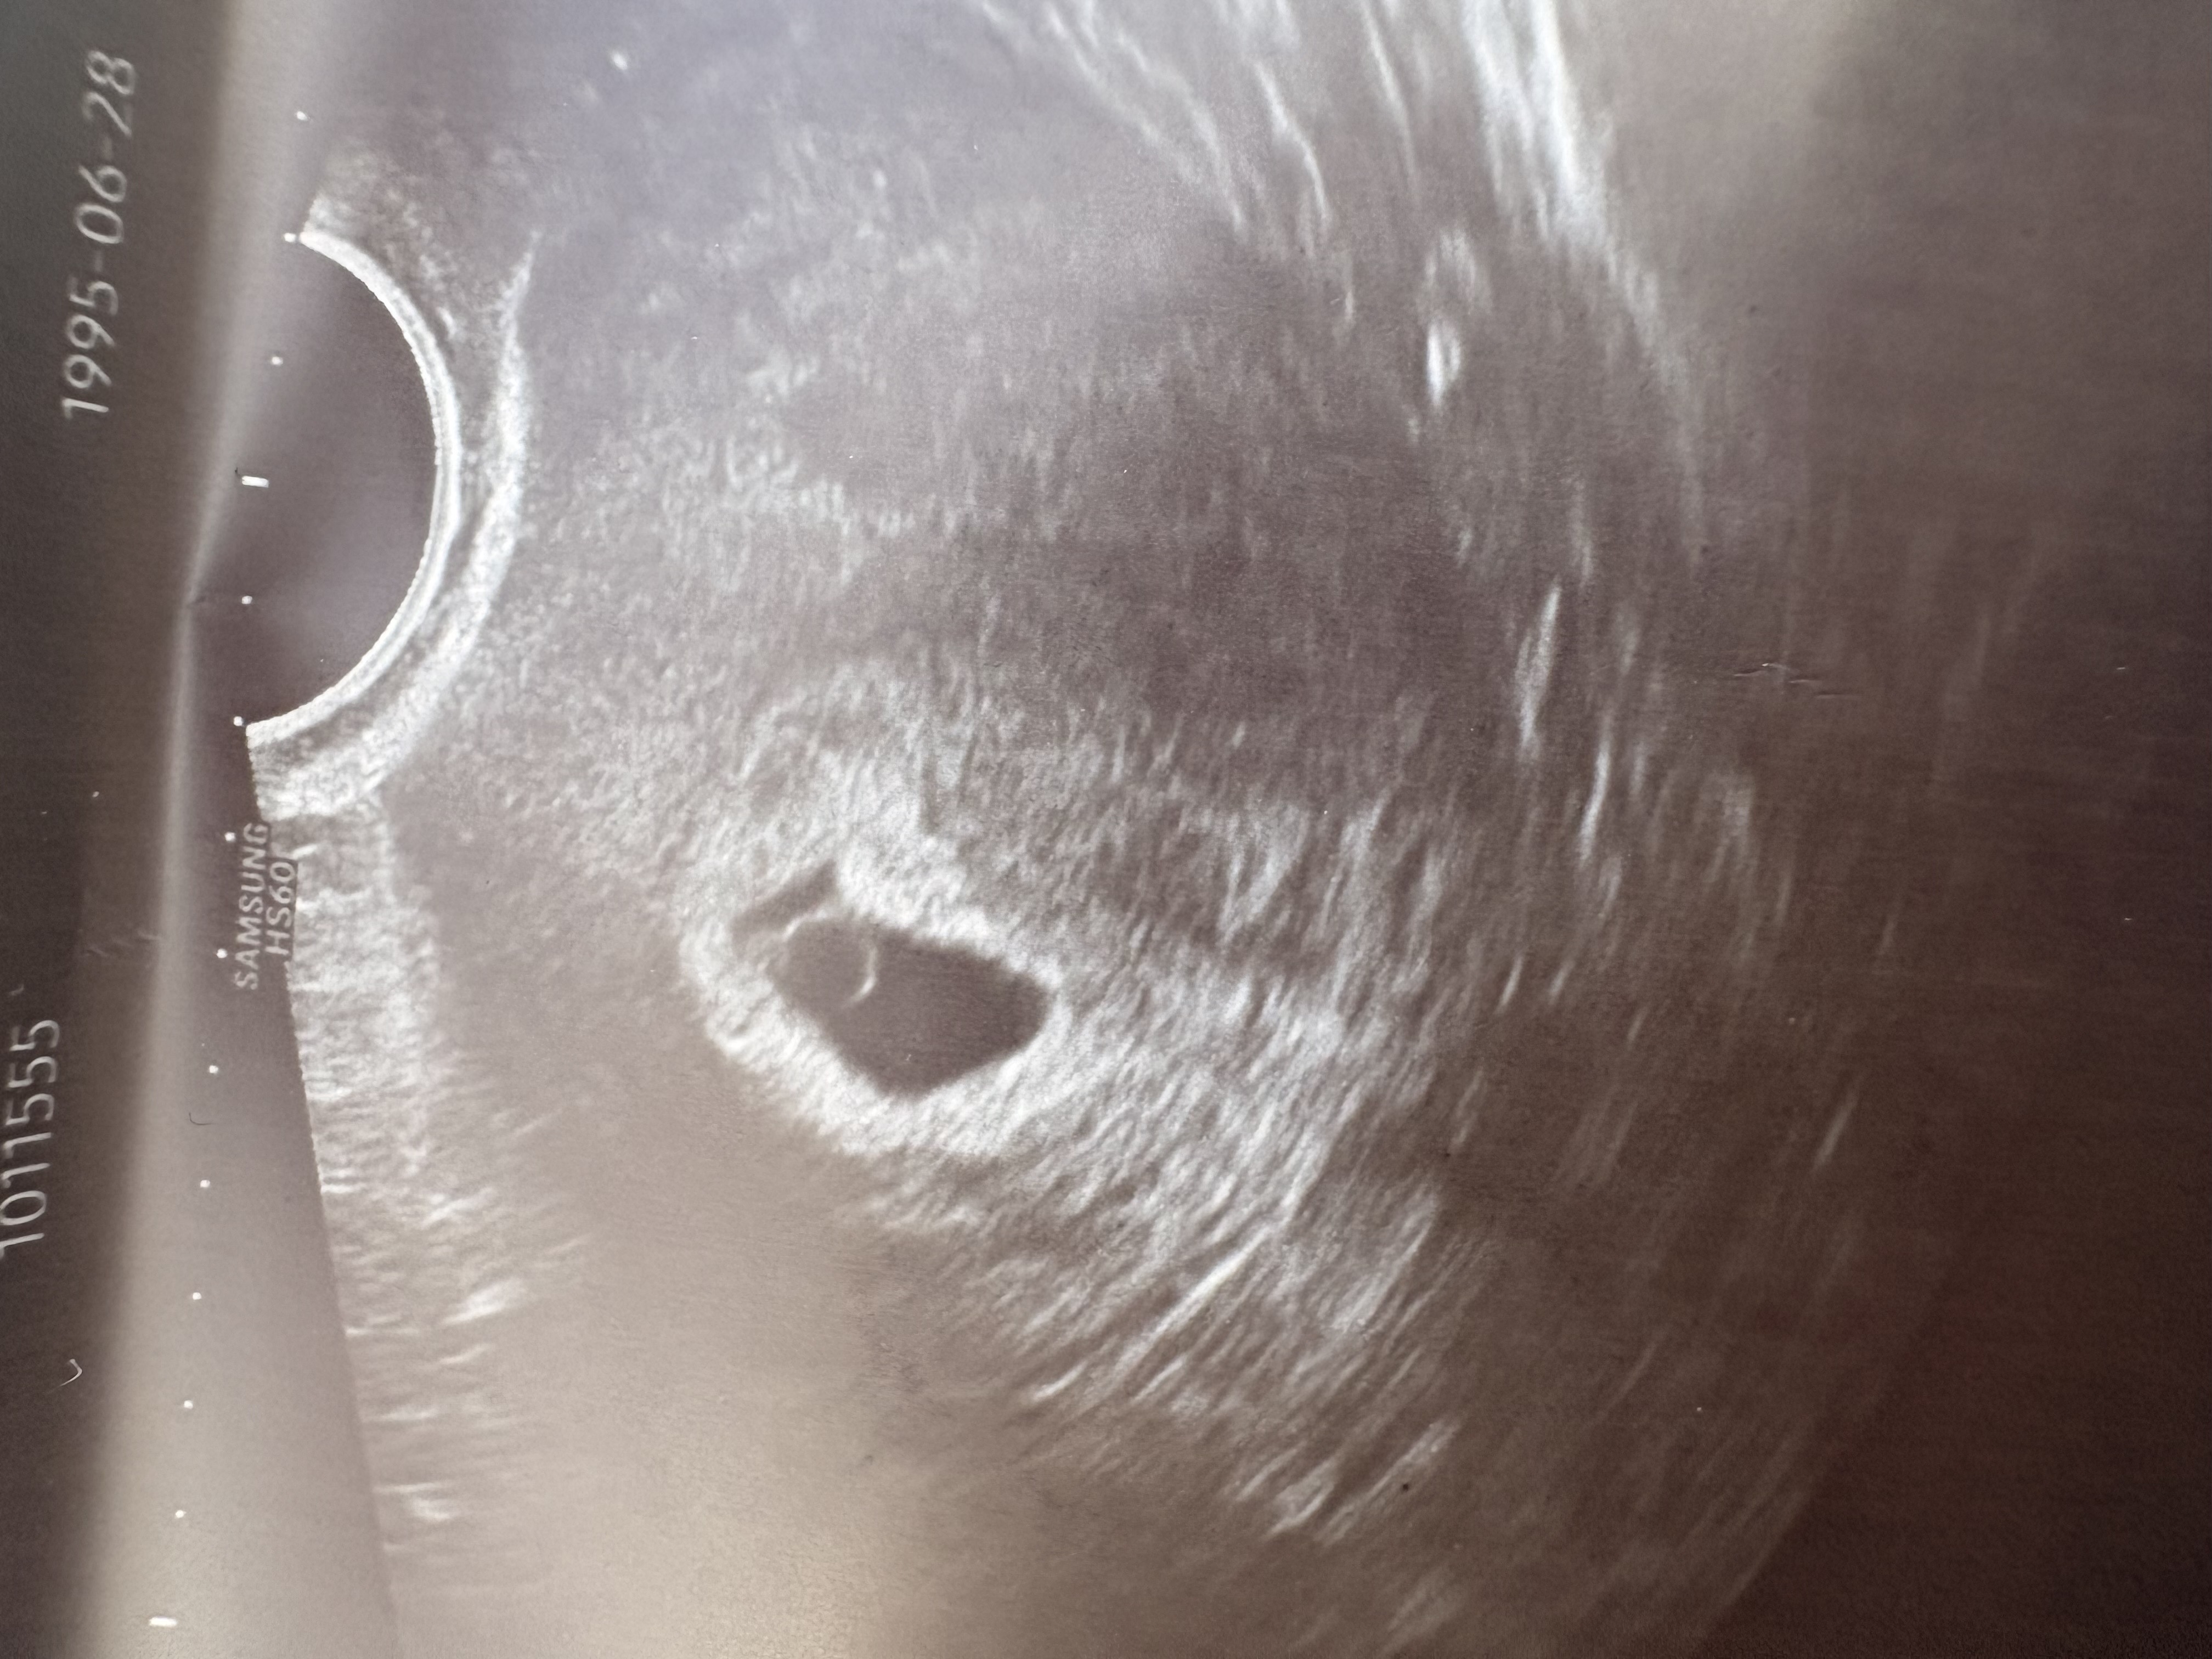

아기집모양좀봐주세요😢

아기집이 동글동글하지않고 찌그러져잇지않나요??ㅠㅠㅠ 다른분들은 다 동글동글이쁜데.. 선생님은 따로 별말씀안하셔서 괜찬은가 싶긴한대 힘들게 생긴아이인만큼 걱정이 되서..🥺

제 아기집도 찌그러져있었는데 다음에 가니 아기집이 커지면서 동그랗게 이뻐졌고 아기랑 난황까지 확인했어요! 의사쌤이 아무말씀 안하셨으면 모양은 괜찮은 것 같아요 : )